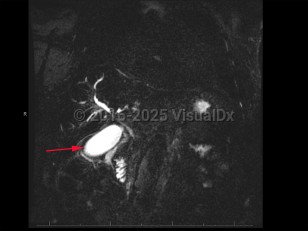

Cholangiocarcinoma refers to biliary tree malignancies, primarily adenocarcinomas, of epithelial cell origin. They are typically categorized as intrahepatic, perihilar, or distal.

Patients with cholangiocarcinoma will often have elevations in their liver function tests (total and direct bilirubin) and liver enzymes (aspartate transaminase [AST], alanine transaminase [ALT], alkaline phosphatase), although these are nonspecific findings. Elevations in cancer antigen (CA) 19-9, a tumor marker, can be suggestive of cholangiocarcinoma but are limited by nonspecificity. Diagnosis typically requires tissue sampling via endoscopic retrograde cholangiopancreatography (ERCP) with brushing.